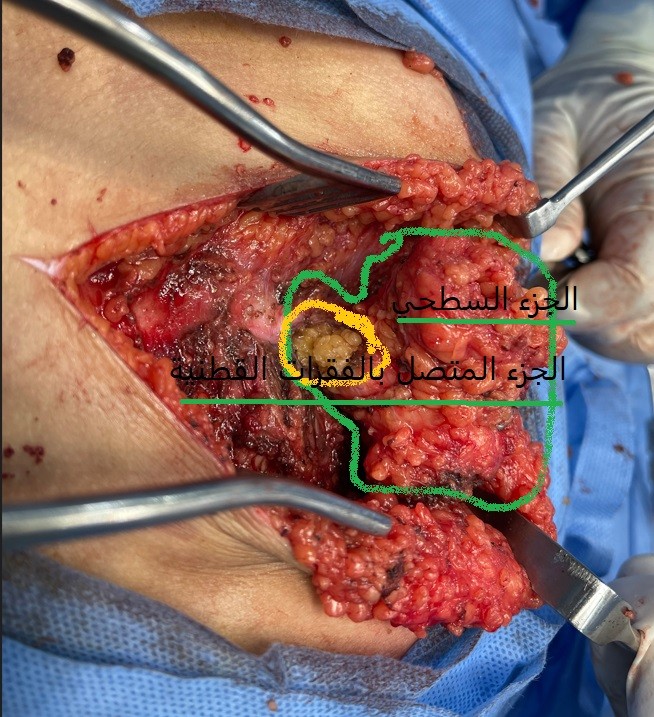

صور من اجراء جراحة لطفلة عامان تعاني من بروز جانبي اسفل الظهر سببه ورم دهني متصل بكيس الاعصاب بالفقرات القطنية و العجزية